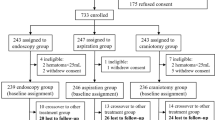

From January 2017 to January 2020, 60 patients (30 males and 30 females, aged 38–83 years) with ICH who were admitted to the Department of Neurosurgery of Tangdu Hospital (Air Force Medical University, Xi’an, China) and Dalang Hospital (Dongguan, Guangdong, China) with complete medical records were selected. All the patients had signed the informed consent before surgery; the coma patients were signed by their immediate family members. Patients were selected according to the following criteria: (1) spontaneous ICH in the basal ganglia; (2) hematoma volume > 30 mL; (3) Glasgow Coma Scale (GCS) > 4, no cerebral hernia and stable vital signs; (4) age > 18 years. The following exclusion criteria were applied: (1) ICH caused by intracranial aneurysms, cerebral arteriovenous malformations, and other brain diseases; (2) any previous history of serious heart, liver, kidney, or other substantial organ dysfunction diseases; (3) coagulation dysfunction; (4) patients with AIDS or other immunodeficiency diseases; (5) lost follow-up. Thirty patients with ICH that were treated with neuroendoscopic surgery guided by 3D-printed navigation technology were categorized as the experimental group (n = 30). The other 30 patients were treated by neuroendoscopic surgery guided by hand-painted localization on the patient’s body surface according to the CT marks composed the control group (n = 30). Patients were followed up for 6 months from the date of surgery. The basic preoperative data of the patients in the two groups are listed in Table 1.

A total number of 60 patients with ICH were enrolled in the study and were divided into two groups: 30 patients treated with neuroendoscopic surgery guided by 3D-printed guidance plate technology were allocated to the experimental group and 30 patients treated with neuroendoscopic surgery guided by hand-painted on the patient’s body surface according to the marks of CT were included to the control group. The preoperative data of the two groups were collected and sorted out (summarized in Table 1); the demographic and clinical features did not significantly differ between the two groups.